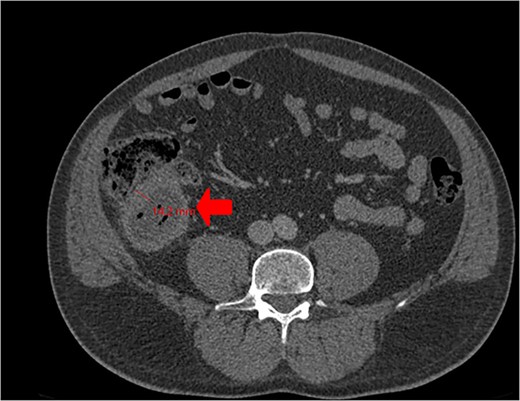

A CT scan showed an oval, 13 × 5.2 cm mass in the right iliac fossa arising from the cecum and running upward, with a thick, edematous wall, fluid, gaseous content, and extensive fat stranding. There was no free fluid and no dilation of bowel, suggesting appendicitis (Figs 1 and 2). Due to these findings, the patient underwent an emergency laparoscopic appendectomy that was converted to open laparotomy. The patient ended up with a right hemicolectomy instead of appendectomy as the appendix could not be separated from the mass, with no separation line between the mass and the cecum. The mass (Fig. 3) measured 10 × 7 × 7 cm and had a thick wall and pyogenic membrane.

Cross-sectional CT view shows the mass measuring 13 × 5.2 cm with significant wall thickening measuring 14.2 mm and fat stranding. The contents are a mixture of fluid and gas, consistent with appendicitis.